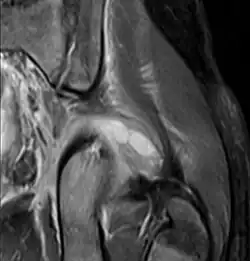

Coronal fat suppressed post contrast image showing a multiloculated bacterial abscess in the left gluteus minimus muscle due to tropical pyomyositis.